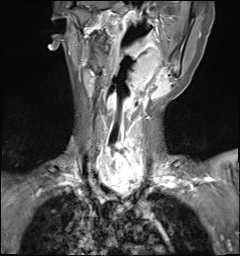

2个多月前,9岁的男孩诚诚出现咳嗽、喘息,在当地医院就诊,一直未见好转,后因咳嗽、气促加重,伴呼吸困难,在当地医院住院治疗,行呼吸机辅助通气,仍有呼吸困难进行性加重并出现发热情况,当地医院立即联系我院,于9月19日在120医护人员的陪同下转入湖南省儿童医院重症监护室,告病危、予气管插管机械通气等对症治疗。9月22日,启动全院大会诊,耳鼻咽喉头颈外科、B超室、普外科、麻醉手术科、放射科等专家仔细分析了病情,考虑恶性肿瘤可能性大,诊断为甲状腺癌并转移?大气道狭窄,呼吸道梗阻,呼吸衰竭,休克等,颈胸部MRI平扫+增强示局部肿块3.8cmx4.0cmx5.2cm,气管受肿瘤侵犯,双肺内多发转移瘤可能性大。MDT团队专家一致认为,像诚诚这种病情进展迅速,严重侵犯气道的临床上比较罕见,它增加了甲状腺癌手术的难度和风险。